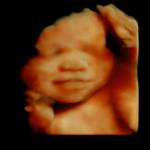

image